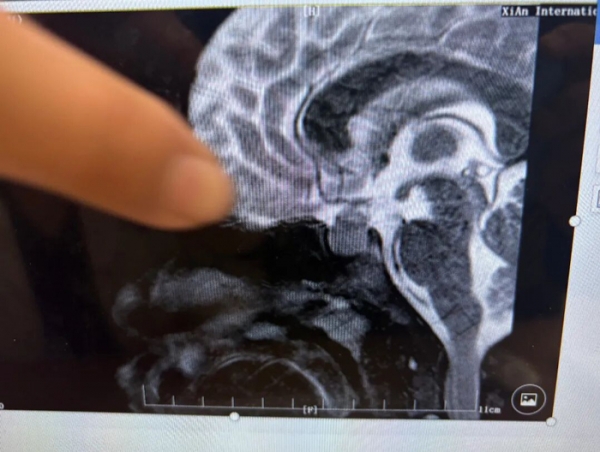

·垂体磁共振:有一个1.7厘米大小的占位,影像科报了"垂体大腺瘤"。

神经外科的医生看了片子说:"这个垂体占位,泌乳素不高,没有溢乳,也不像典型的垂体瘤。虽说垂体瘤直径超过1cm时有手术指征,但术后孩子可能会生活质量受影响,先别急着手术。"

·垂体的占位,完全消失了!